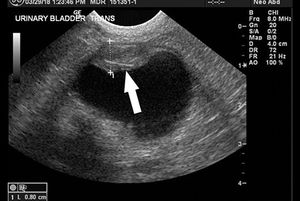

Examine the ultrasonograms, study the exam findings, and see if you can name the cause in this feline patient with hematuria and recurrent UTIs.

An intervention to remove urinary stones didn't alleviate this bichon frises's stranguria. See if you can spot the cause in this ultrasonogram.